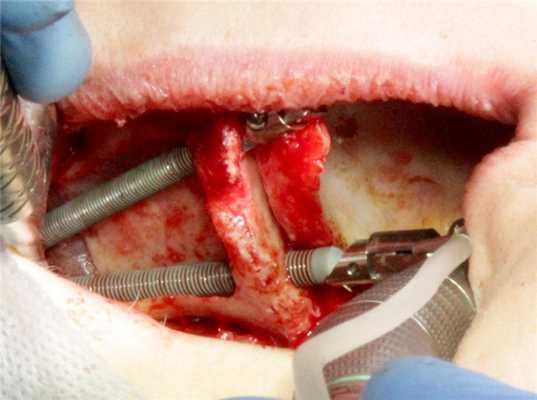

- Разрез и скелетирование переднебоковой стенки верхней челюсти (фото 5)

- Формирование костно-надкостнично-слизистого лоскута в области боковой стенки верхнечелюстной пазухи, отслаивание слизистой оболочки пазухи (фото 6)

- Смещение лоскута кнутри и формирование доступа к скуловой кости (фото 7)

- Скелетирование внутренней поверхности скуловой кости, создание метки для верхнего имплантата (фото 8)

- Препаровка костного ложа для верхнего имплантата (фото 9)

- Установка верхнего имплантата в позицию 1.3 (фото 10)

- Препаровка костного ложа для нижнего имплантата (фото 11)

- Установка нижнего имплантата в позицию 1.6 (фото 12)

- Примерка и установка мультиюнитов и ушивание (фото 13)

- Аналогичные действия были выполнены с левой стороны с установкой имплантатов в позиции 2.3 и 2.6 (фото 14)